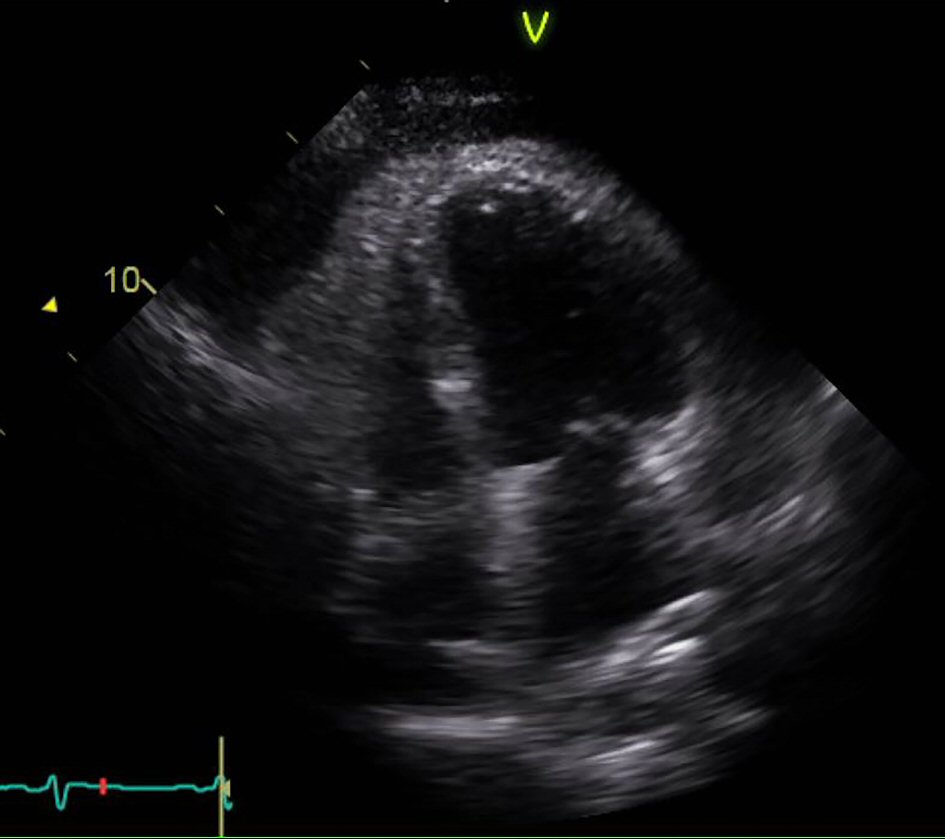

Figure 4. Echocardiogram apical view showing right ventricular collapse in diastole.